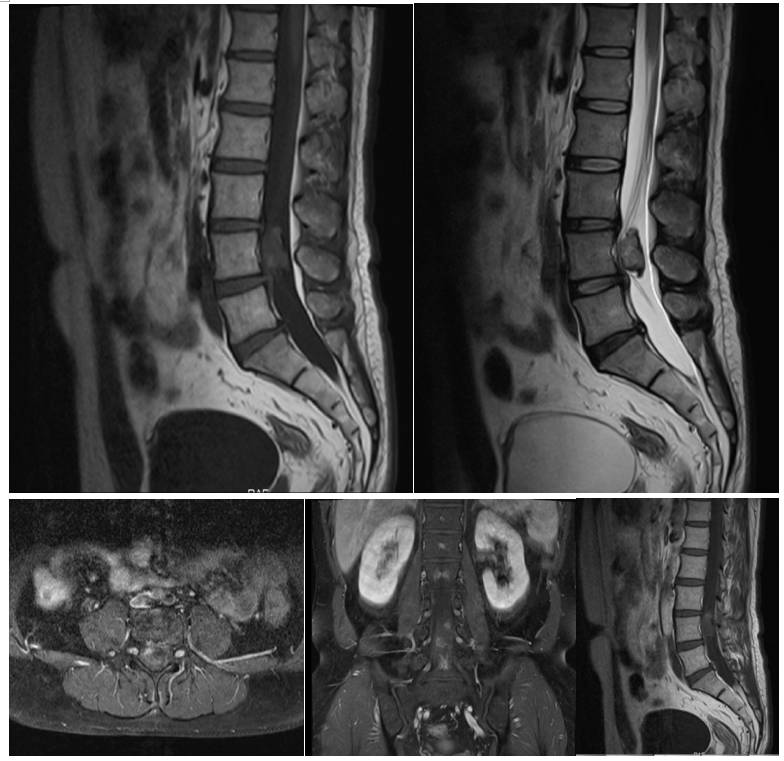

患者术后恢复可,术后左下肢疼痛消失,行走无殊。但出现轻度麻木,考虑神经与钙化壳粘连严重有关。复查腰椎CT及腰椎增强MRI显示肿瘤基本全切除(图2)。

图2. 术后CT及MR